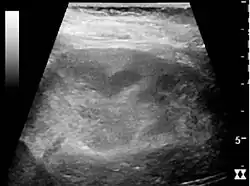

In medical imaging, the acute changes in the kidney are often examined with renal ultrasonography as the first-line modality, where CT scan and magnetic resonance imaging (MRI) are used for the follow-up examinations and when US fails to demonstrate abnormalities. In evaluation of the acute changes in the kidney, the echogenicity of the renal structures, the delineation of the kidney, the renal vascularity, kidney size and focal abnormalities are observed.[16] CT is preferred in renal traumas, but US is used for follow-up, especially in the patients suspected for the formation of urinomas. A CT scan of the abdomen will also demonstrate bladder distension or hydronephrosis. However, in AKI, the use of IV contrast is contraindicated as the contrast agent used is nephrotoxic.